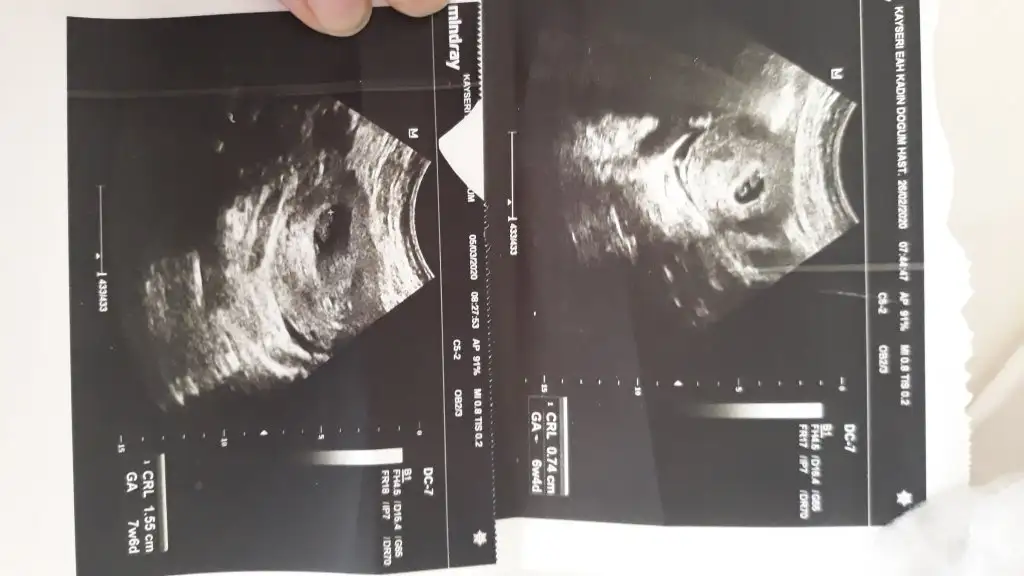

eklediğim fotolar vajinal ultrasondan ve burada 5+4 haftalık:)

Ben kese konumunu pek tuttugunu sanmıyorum ben nub tahmini yapıyorum 11 yada 12 hafta olmalı kesede yolk saç nerde ise yani sag tarafta hafif kabarık beyaz parlak alan sagda tabi siz vajinal bakıldıgı için asıl solda olmuş oluyor karından bakılınca asıl sol olmuş olacaktı ve erkek 😊

Ben şimdilik tahmininizin kısmen tuttuğunu söylemek için yazdım özellikle.. ultrason fotosunu da ekliyim 12.hafta içinde nub teoremiyle tahminlerinizi alıyım böylece birlikte teyit etmiş olalım şimdiden teşekkür ediyorum :)